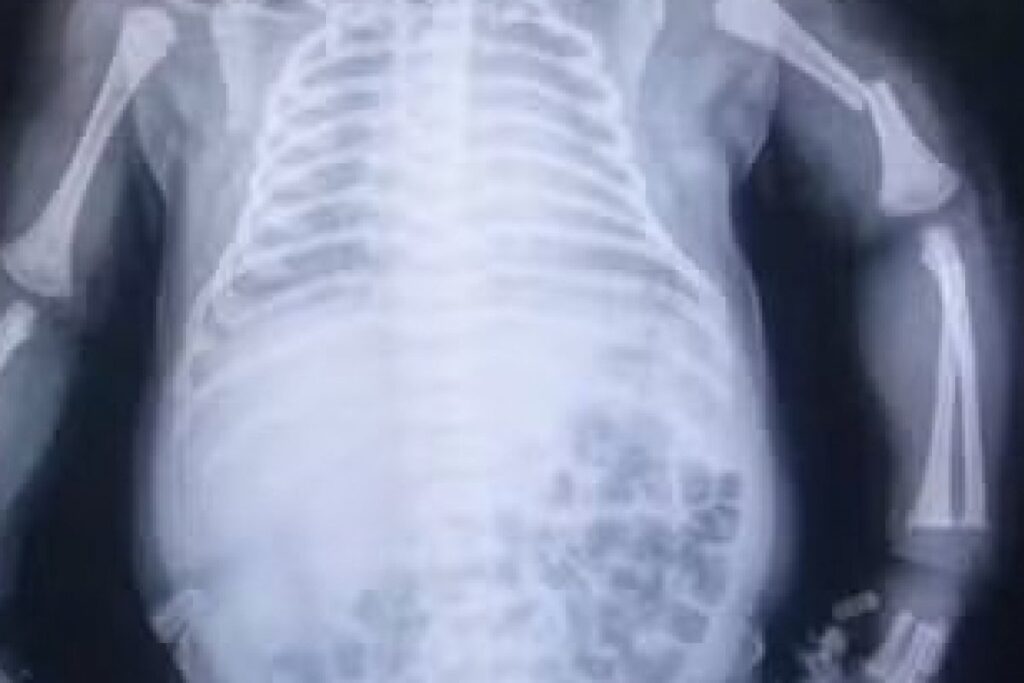

O bebê nasceu às 19h49, pesando 4,3 kg, e apresentou asfixia perinatal, precisando de manobras de reanimação logo após o nascimento.

Segundo o relatório médico, além da fratura, há suspeita de lesão no plexo braquial direito, o que impede o bebê de movimentar os braços normalmente. O documento recomenda uso de dipirona sistêmica, imobilização do membro afetado e acompanhamento com ortopedia pediátrica.